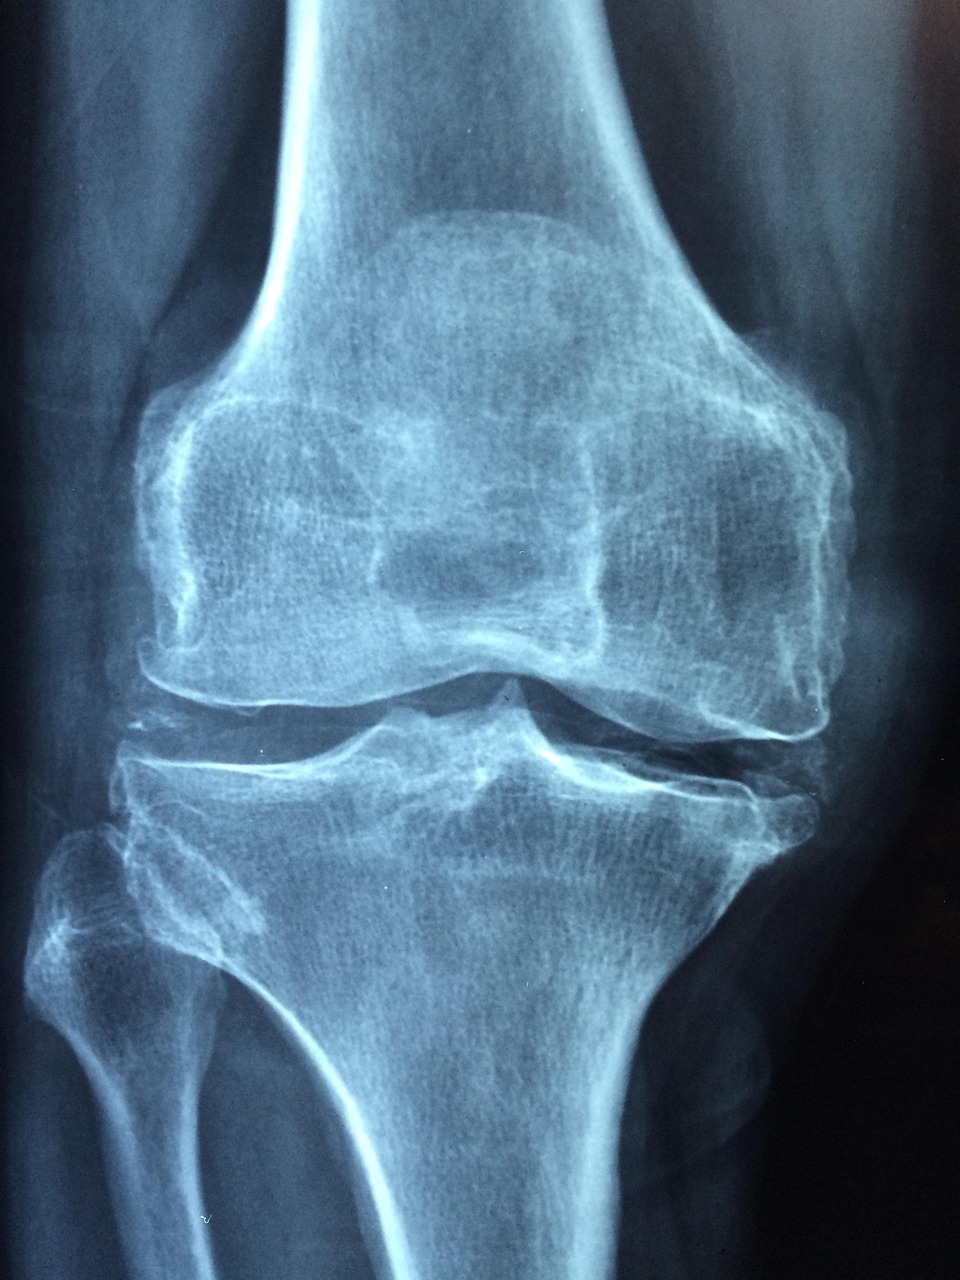

Arthritis in Düren ist der Oberbegriff für entzündungsbedingte Gelenkerkrankungen, während Arthrose den Verschleiß des Gelenkknorpels beschreibt.

Der Begriff Arthrose oder Arthrosis bezeichnet einen degenerativen Gelenkverschleiß, Gelenkerkrankung, Gelenkabnutzung

Mit den Folgen einer Arthrose hat mit zunehmendem Alter fast jeder zu kämpfen. Die Ursache ist eine natürliche Abnutzung der Gelenkknorpel durch lebenslange Belastung.

Arthritis hingegen ist eine entzündliche Gelenkerkrankung, die diverse Ursachen haben kann, so kann auch eine Arthrose eine Entzündung entwickeln und zu einer Arthritis werden.

Arthrose ist eine Volkskrankheit, weltweit ist sie die häufigste Gelenkerkrankung.

Rund fünf Millionen Deutsche sind betroffen. Obwohl zunehmendes Alter als Risikofaktor für den Gelenkverschleiß gilt, sind nicht nur alte Menschen von Arthrose betroffen. Besonders häufig entstehen die Beschwerden in Knie- und Hüftgelenken.